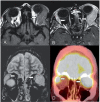

Amyloidosis comprises a rare spectrum of protein deposition diseases that diffusely or focally affect any organ. Amyloid's variable clinical presentation and nonspecific disease course often cause it to evade early diagnosis. This pictorial essay aims to familiarize radiologists with the pathophysiology of amyloidosis, to describe the basic classifications of amyloidosis, and to use multimodality imaging to illustrate its varied appearance throughout the body. This review highlights the diagnostic challenge of interpreting radiographic studies in patients with hematologic malignancies and concurrent amyloidosis. Radiologists should consider amyloid in chronically ill patients or patients with hematologic malignancies who have unusual/unexpected imaging findings.